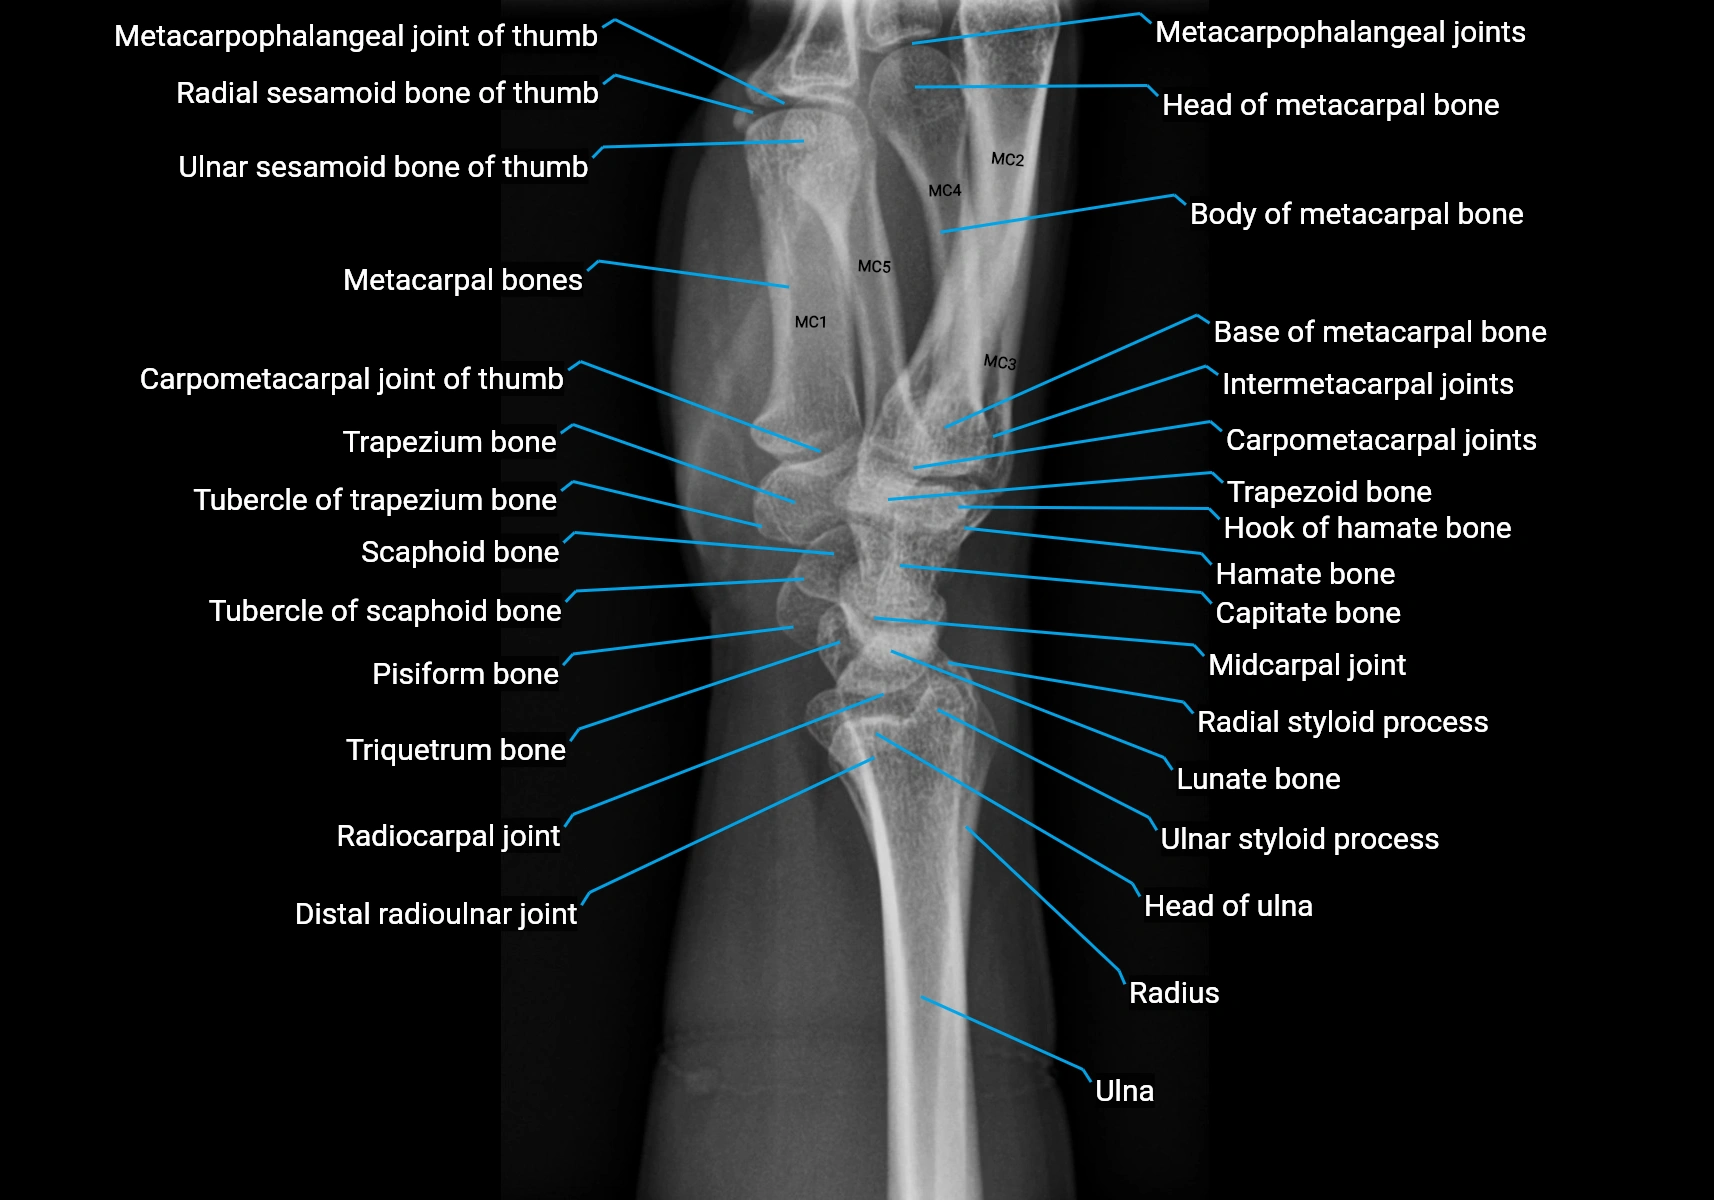

CT Appearance

Non-Contrast CT:

• Muscle: soft-tissue density, well defined in the hypothenar region.

• Tendon: linear low-density structure extending to the base of the little finger.

• Calcification or chronic scarring may appear as localized high-density foci.

• Useful for assessing bony attachment sites at the pisiform and proximal phalanx.